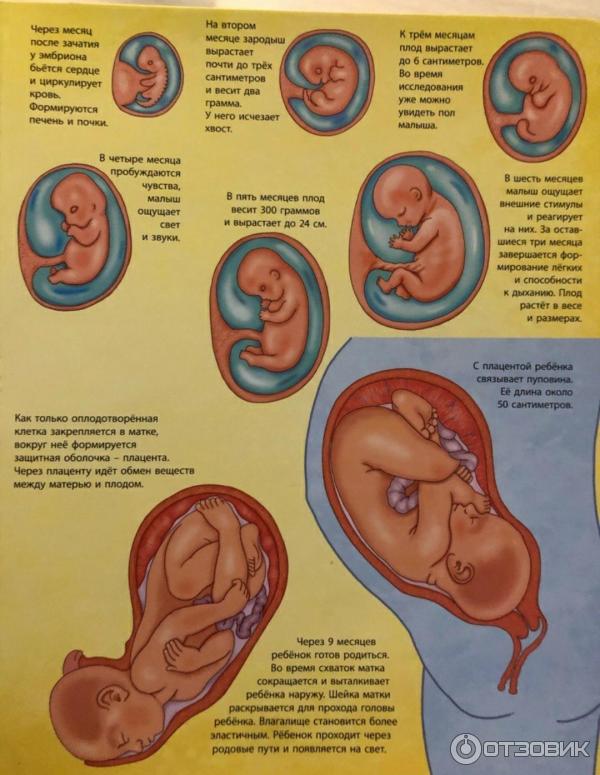

Формирование Плода в Первом Триместре: Важные Этапы